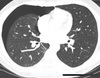

Mulher, 45 anos, dispneia e tosse seca há 5 dias. Passado de transplante pulmonar bilateral.

Bronquiolite obliterante (Bronquiectasias e espessamento das paredes brônquicas + Aprisionamento aéreo + Opacidades em vidro fosco -> Atenuação em mosaico)